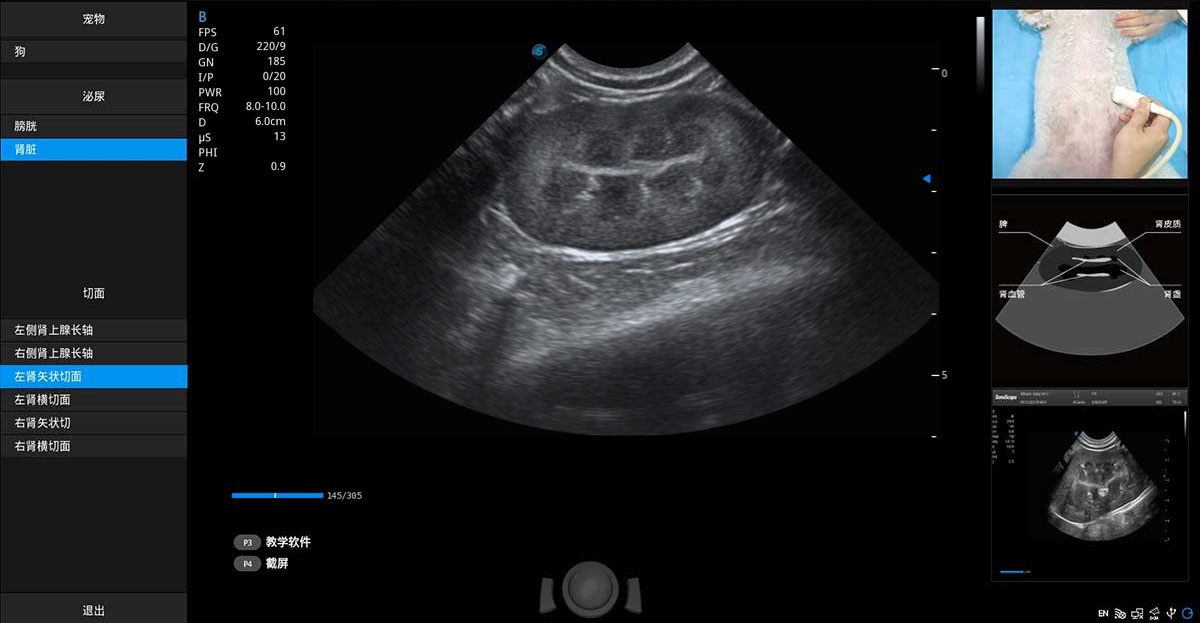

ProPet 80 專為動(dòng)物醫(yī)生設(shè)計(jì),對(duì)不同的動(dòng)物體型和生理結(jié)構(gòu)作出了針對(duì)性的優(yōu)化。通過(guò)動(dòng)物影像專用軟件,可滿足個(gè)性化的應(yīng)用需求,幫助動(dòng)物醫(yī)生獲得更精確的診斷數(shù)據(jù)。

提供解剖示意圖、標(biāo)準(zhǔn)超聲圖像、掃查手法涂和操作者實(shí)時(shí)檢查圖像,指導(dǎo)操作者進(jìn)行標(biāo)準(zhǔn)切面的正確掃查。